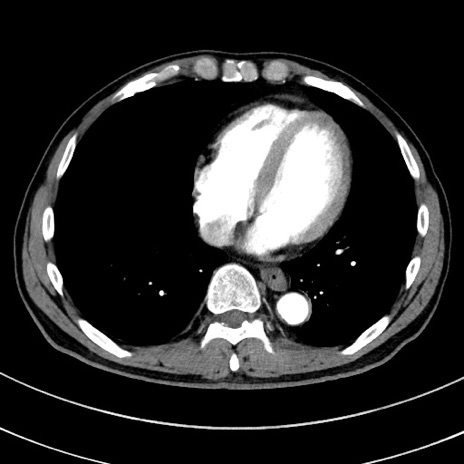

冠状断像

【症例】 60歳代男性

【主訴】 黒色吐物

【現病歴】 4日前から嘔気自覚、2日前の朝食後にも嘔気あり、自分で手で嘔吐反射起こし嘔吐したところ血が混ざっていたため受診。

【既往歴】 5年前汎発性腹膜炎を伴う急性虫垂炎で手術、高血圧、前立腺肥大症、高脂血症

【身体所見】 腹部正中に手術癩痕あり 腹部平坦・軟圧痛なし膨満感あり

【データ】WBC 8400、CRP 4.54